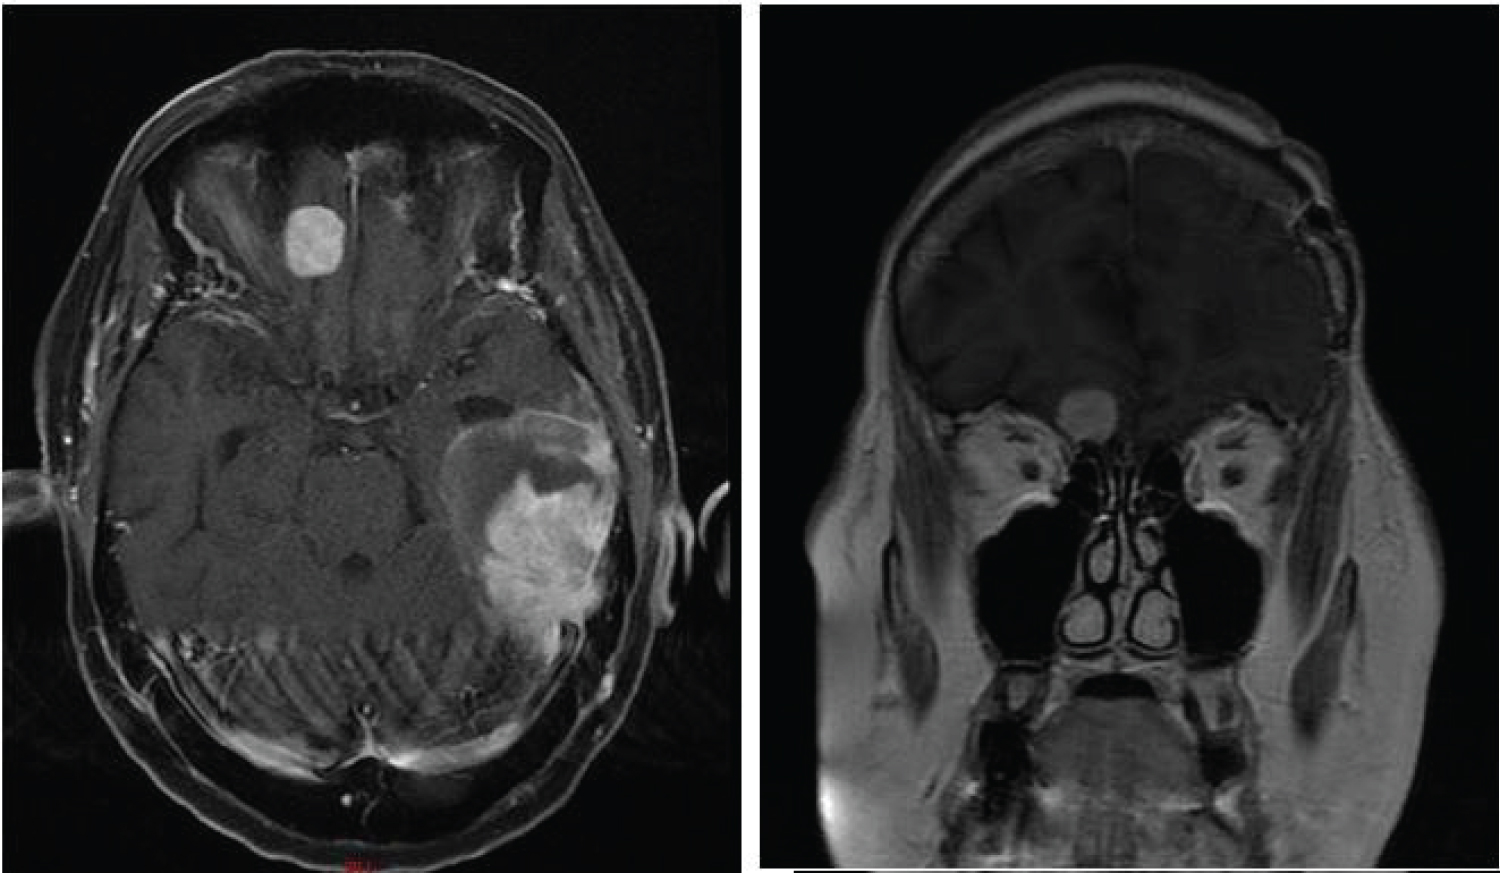

Approximately six months after completion of adjuvant therapy, she developed expressive aphasia and a MRI of the brain revealed a new left sided temporal lobe mass outside the previously treated area (Figure 3).

Figure 3: Eight months after her initial resection, an MRI was performed to evaluate new expressive aphasia. Gadolinium enhanced T1-weighted images showed development of a 3 cm new left temporal lobe mass. View Figure 3

One month later, she developed right frontal headaches and a final MRI of the brain revealed progression of the metastatic deposit in the right frontal lobe (Figure 7).

Figure 7: Axial and coronal MRI images showing enlargement of the left temporal mass and right frontal lobe mass. View Figure 7